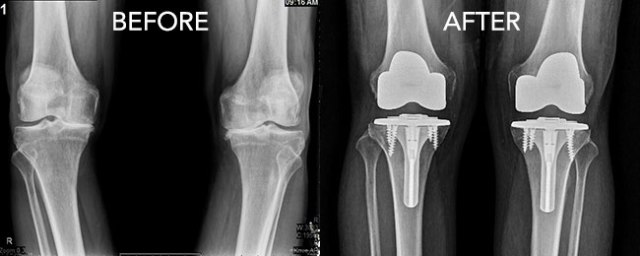

The department is headed by Dr. Rajinder Rajan (M.S, M.ch Orthopaedics) who is working as Consultant Orthopaedician in Amritsar and around, for the last more than 15 years. He is having experience of about 2000 Hip and Joint replacements. He is expert in managing Trauma patients. He is giving 24 x 7 availability in hospital to manage emergencies. The Corporate Hospital team is committed for managing your care and following your program carefully.